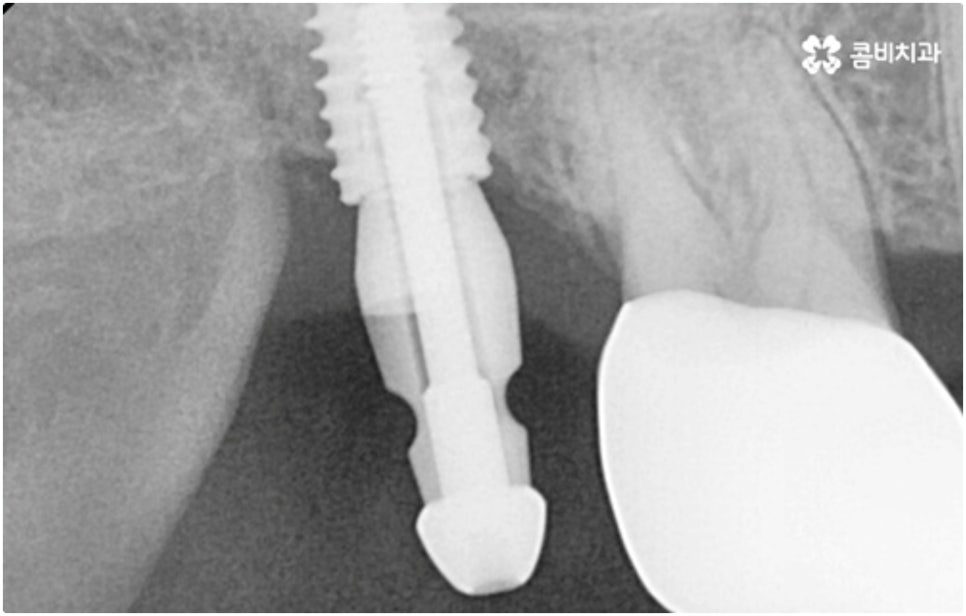

임플란트 시술이 환자분들의 잇몸뼈에 직접 고정을 시키는 방법인 만큼 개개인의 치주 상태, 구강 내부 구조 등을 면밀하게 살펴보고 치료 계획을 세워야 하며 그 밖에도 치아가 빠진 지 얼마의 시간이 흘렀는지, 장기적으로 복용 중인 약이 있는지 등 영향을 줄 수 있는 모든 관련 상황을 종합적으로 고려하여 환자분들에게 딱 맞는 어금니임플란트 시술을 무리하지 않게 진행하는 것이 중요한 체크 포인트라고 할 수 있는데요. 그렇기 때문에 먼저 3D CT를 이용한 정밀한 검사를 통해 어떤 종류의 임플란트를 어떻게 진행할지 신중하게 검토해야 하며 또한 풍부한 노하우와 뛰어난 기술력을 갖추고 있는 의료진과 함께 충분한 사전 상담을 하실 필요가 있습니다.

식립 성공률 및 지속적인 안정성을 높이기 위해서는 초기 고정이 잘 이루어져야 하는데 만약에 식립 바탕이 되는 잇몸뼈의 상황이 좋지 않다면 이와 관련된 치료를 먼저 해 줘야 하는 거예요. 예를 들어 치주 질환이 심하다면 이를 깨끗하게 치료해 주는 것이 우선시 되어야 하고, 잇몸뼈의 높이나 밀도 등이 부족한 경우에는 뼈이식 과정을 통해 이를 먼저 보충해 줄 필요가 있어요. 또한 윗어금니가 빠진지 오랜 시간이 지나 이미 골흡수가 일어나고 상악동이 많이 내려와 있다면 상악동 거상술 및 뼈이식을 한 후 임플란트 식립을 진행해야 할 거예요.

이와 같이 상악의 경우 상악동과 비강저(콧구멍 바닥)까지의 거리 및 신경과 혈관분포, 하악의 경우 하치조 신경 및 하치조관과 이공까지의 거리, 주위 조직 등에 대한 면밀한 검진과 파악이 필요하기 때문에 임플란트 시술을 진행할 때 상하악골 및 주변 조직을 해부학적으로 자세히 체크할 수 있는 정밀 장비 및 담당 의료진의 숙련도가 굉장히 중요한 요소라고 할 수 있어요.

어금니는 저작력이 많이 걸리는 치아이기 때문에 보철물 제작에 있어서도 강한 자극에 잘 견딜 수 있는 튼튼한 재질을 고르는 것이 중요한데 요즘은 이러한 내구성과 함께 심미적인 부분도 함께 고려하는 추세라서 어금니임플란트 시술시 지르코니아 크라운을 선택하시는 분들이 많이 있습니다.